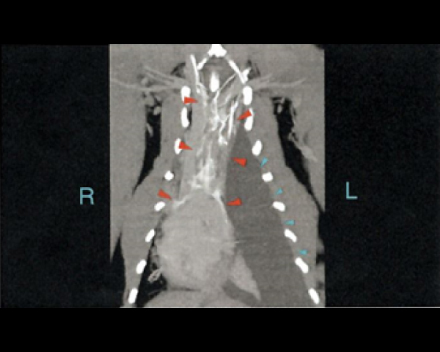

造影CT検査にて腫瘤の浸潤・転移を評価

脾臓の多発性吸収結節像を確認